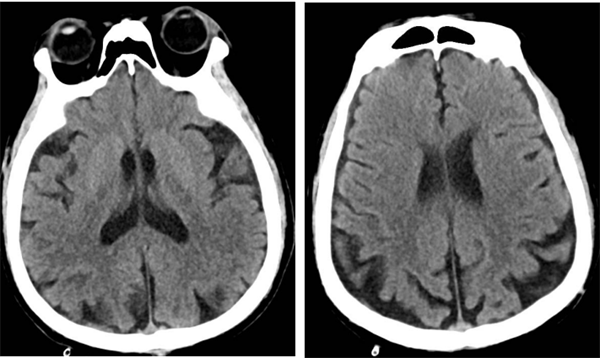

近日,我院神经外科收治了一名74岁高龄且伴有多年高血压、糖尿病史的高危患者何先生(化名)。何先生此前已接受过右侧椎动脉、左侧锁骨下动脉支架植入术,但近期因头晕、左侧肢体乏力等症状再次入院。经过详细检查,医生发现何先生右侧颈内动脉起始部存在重度狭窄,狭窄率高达75%,情况危急。

▲术前脑血管造影

▲术后复查头颅CT

术后,何先生顺利苏醒,回到神经外科病房进行监护治疗,术后7天伤口愈合良好拆线出院。8月何先生来我院复查,DSA检查提示右侧颈动脉狭窄已完全恢复并无再狭窄,头晕及左侧肢体乏力症状也完全缓解了。

▲术后狭窄完全解除